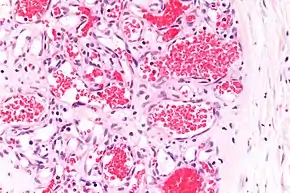

Capillary hemangioma

A precise history of the growth characteristics of the IH can be very helpful in making the diagnosis. In the first 4 to 8 weeks of life, IHs grow rapidly with primarily volumetric rather than radial growth. This is usually followed by a period of slower growth that can last 6–9 months, with 80% of the growth completed by 3 months. Finally, IHs involute over a period of years.[24] The exceptions to these growth characteristics include minimally proliferative His, which do not substantially proliferate[23] and large, deep IHs in which noticeable growth starts later and lasts longer.[24] If the diagnosis is not clear based on physical examination and growth history (most often in deep hemangiomas with little cutaneous involvement), then either imaging or histopathology can help confirm the diagnosis.[21][25] On Doppler ultrasound, an IH in the proliferative phase appears as a high-flow, soft-tissue mass usually without direct arteriovenous shunting. On MRI, IHs show a well-circumscribed lesion with intermediate and increased signal intensity on T1- and T2-weighted sequences, respectively, and strong enhancement after gadolinium injections, with fast-flow vessels.[21] Tissue for diagnosis can be obtained via fine-needle aspiration, skin biopsy, or excisional biopsy.[26] Under the microscope, IHs are unencapsulated aggregates of closely packed, thin-walled capillaries, usually with endothelial lining. Blood-filled vessels are separated by scant connective tissue. Their lumina may be thrombosed and organized. Hemosiderin pigment deposition due to vessel rupture may be observed.[27] The GLUT-1 histochemical marker can be helpful in distinguishing IHs from other items on the differential diagnosis, such as vascular malformations.[22]